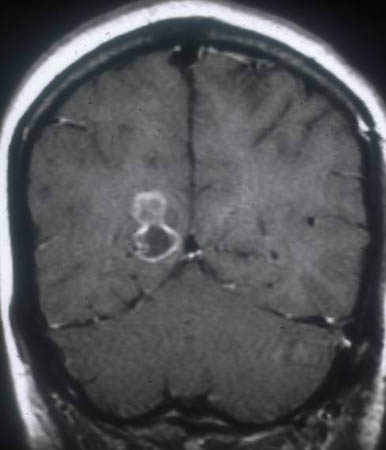

RNM cranioencefálica/da coluna

Exame

A neuroimagem é a base do diagnóstico para a neurocisticercose. A RNM é superior à TC na identificação de cistos extraparenquimatosos e lesões da fossa posterior, mas a TC é melhor na visualização de cistos calcificados.[39] A RNM também pode revelar o escólex que, geralmente, não é visível em TCs. Idealmente, ambos os testes devem ser considerados.

Achados específicos dependem da localização dos cistos (consulte tomografia computadorizada do cérebro, acima).[33][40]

Todos os pacientes com doença subaracnoide devem fazer uma RNM da coluna.[33][Figure caption and citation for the preceding image starts]: Estádio cístico - neurocisticercose: ressonância nuclear magnética (RNM) mostrando lesão cística no lobo frontal; é possível observar um escólex no interior do cistoDo acervo da Dra. Christina Coyle e do Dr. Maheen Saeed; usado com permissão [Citation ends].

[Figure caption and citation for the preceding image starts]: Estádio granular - neurocisticercose: RNM mostrando lesão com realce sem edema perilesionalDo acervo da Dra. Christina Coyle e do Dr. Maheen Saeed; usado com permissão [Citation ends].